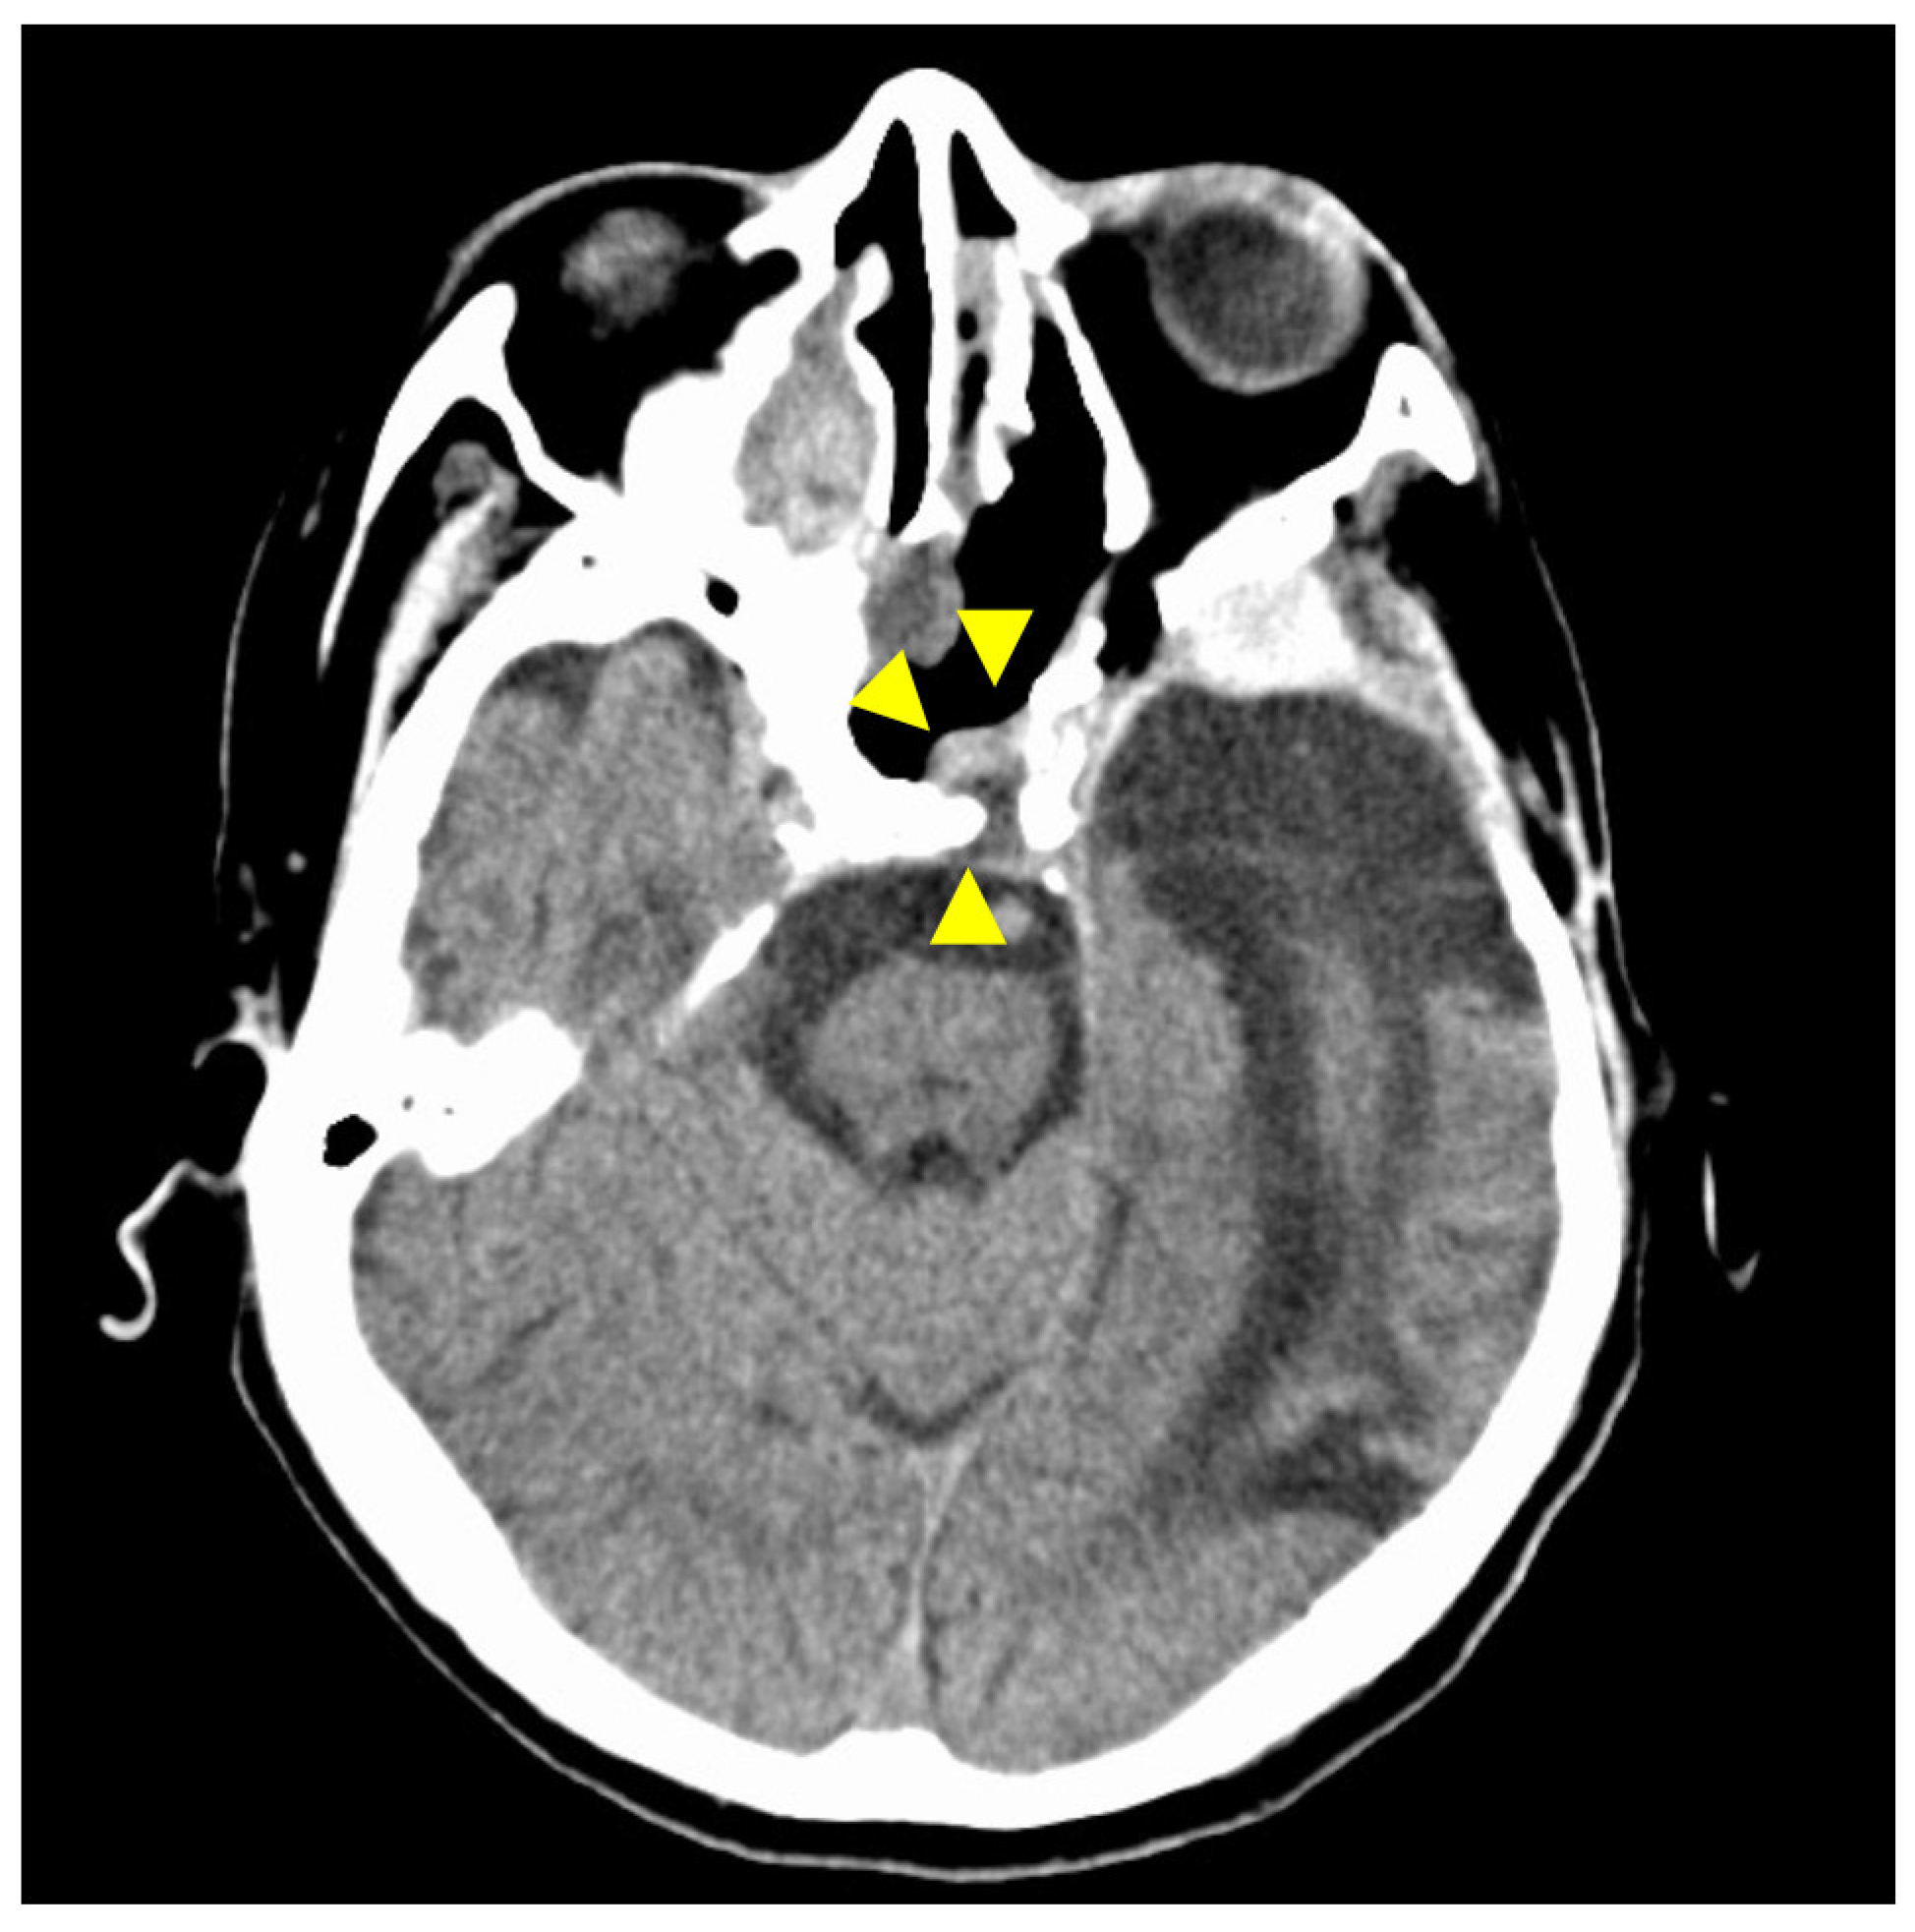

Figure 1. Preoperative contrast-enhanced computed tomography (CT) findings. Axial section (A) and coronal (B) images are shown. An isodense area with surrounding bone destruction is observed in the left sphenoid sinus, and no surrounding bone is observed around the internal carotid artery (ICA). Arrowheads indicate tumors.